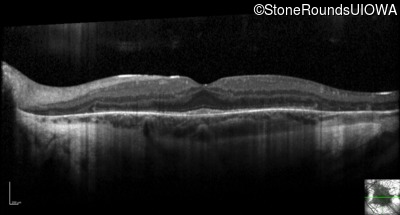

Optical Coherence Tomography - Right - 20/32

Exemplar / OCT Stack